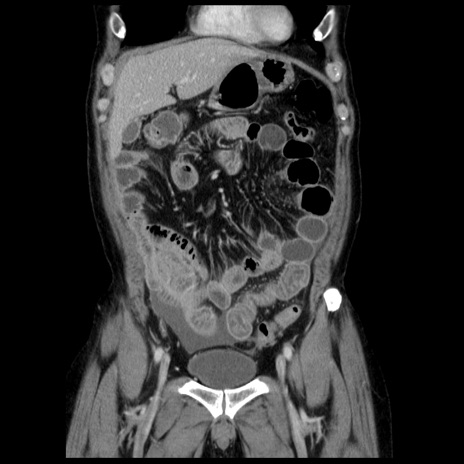

横断像

【症例】40歳代男性

【現病歴】2日前から胃痛あり。徐々に周期的な激痛に変化した。本日になっても激痛があるため受診。

【身体所見】意識清明、BT 38-39℃台あり、腹部:膨満、やや硬、右下腹部に圧痛あり。

【データ】WBC 8500、CRP 23.26